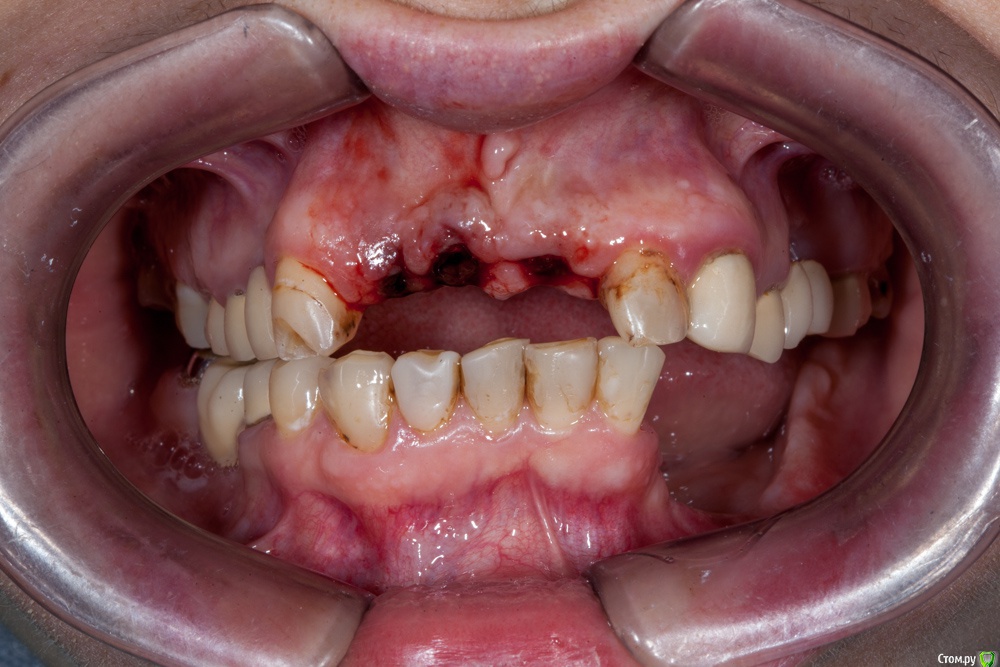

Игнатович Опубликовано 2 марта, 2015 Поделиться Опубликовано 2 марта, 2015 Доброго времени суток. Сам я ортопед. Вашему вниманию представляю пару снимков и хочу спросить совета: что делать с левой стороной нижней челюсти???Планируется замена МК конструкций на верхней челюсти, изготовление ДЦ коронок на инд абатментах на 11,21,22, ламинаты-полукоронки-коронки на фронт верх и низ... Мост на 45-47 нас покинет, так же, как и сам 47. Больше всего волнует низ левая сторона, атрофия значительная, узкий альвеолярный гребень, зубы удалены около года. Для пациентки более предпочтительна несъёмная конструкция.Варианты, которые приходят в голову:-костная пластика и имплантация двухэтапными имплантатами? (где брать костные блоки и мягкие ткани, гарантирован ли результат?? и через сколько после операции можно будет протезироваться?) -имплантация одноэтапными имплантатами и немедленная нагрузка металлопластмассовой шиной (но какова получится эстетика и не вынесет ли она коронки вместе с имплантатами)???-съемник (как вариант бюгельный ацеталовый)???СПАСИБО!) Ссылка на комментарий